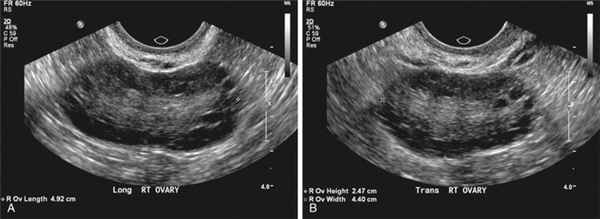

Для оценки морфологии яичников проводят УЗИ органов малого таза .

- ультразвуковое исследование при поликистозе яичников — на УЗИ выявляется характерное строение яичников с большим количеством (12 и более) мелких фолликулов от 2 до 9 мм в яичнике.

- ультразвуковая диагностика (УЗИ) органов малого таза — при поликистозе яичников на УЗИ четко видны увеличенные яичники с большим количеством мелких фолликулов;